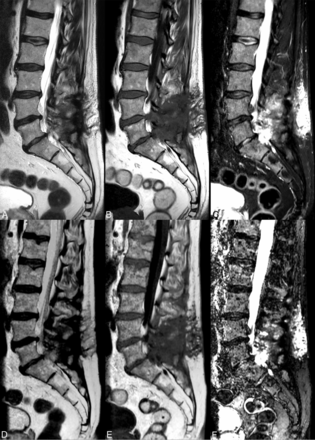

Artifacts consisting of white pixels/spike noise across contrast views and flow artifacts were more common in the synthetic sequences (except proton-density), especially in synthetic STIR (Fig 3).

Conventional FSE T2 (A), spin-echo T1 (B), and STIR (C) images show a postsurgical lumbar spine with postoperative changes in the posterior soft tissues. The synthetic images (D–F) depict these changes with similar detail. Note the dirty appearance of the vertebral bodies observed in the synthetic reconstructions and flow artifacts from the aorta, especially in the synthetic STIR sequence.